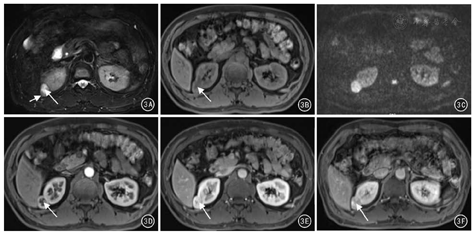

MRI检查5例5个病灶。MRI平扫:T1WI病灶呈等、低信号,T2WI病灶呈混杂稍高信号,DWI病灶呈混杂高信号;1例见囊状低密度影。见图3A,图3B,图3C。增强扫描:皮髓质期病灶明显强化,实质期及排泄期强化程度低于肾皮质;1例病灶内见"星芒状"瘢痕,并呈延迟性强化(图3D,图3E,图3F)